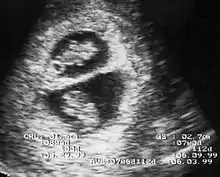

λ Sign in 8 week pregnancy

By performing an obstetric ultrasound at a gestational age of 10–14 weeks, monochorionic-diamniotic twins are discerned from dichorionic twins. The presence of a "T-sign" at the inter-twin membrane-placental junction is indicative of monochorionic-diamniotic twins (that is, the junction between the inter-twin membrane and the external rim forms a right angle), whereas dichorionic twins present with a "lambda (λ) sign" (that is, the chorion forms a wedge-shaped protrusion into the inter-twin space, creating a rather curved junction).[4] The "lambda sign" is also called the "twin peak sign". At ultrasound at a gestational age of 16–20 weeks, the "lambda sign" is indicative of dichorionicity but its absence does not exclude it.[5]